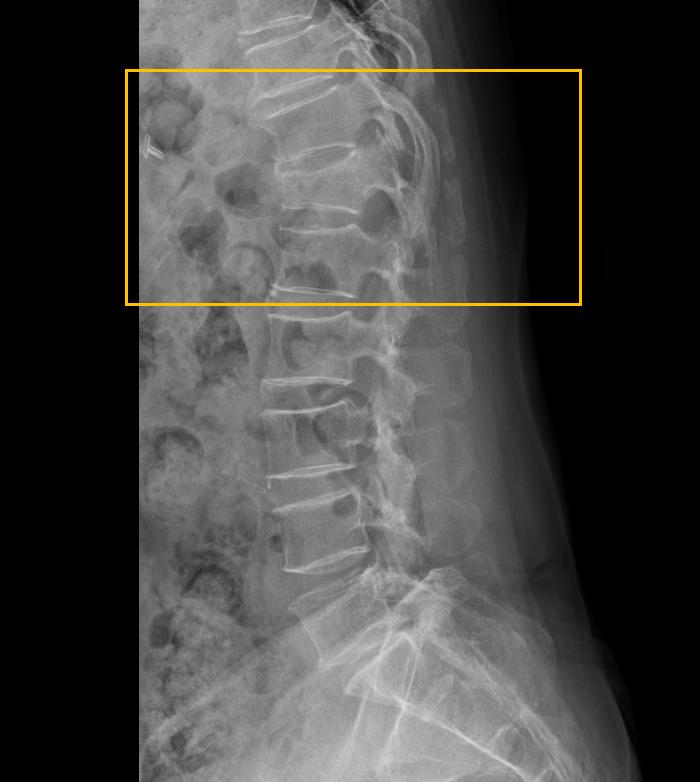

4.png 이미지

위 사진은 압박골절이 된 추체 자체의 각도 변형을 측정한 것으로 2018년 이전 보험의 경우 적용이 가능합니다.

5.png 이미지

2018년 이후 가입한 보험의 경우 cobb's 각도에 의하여 각변형을 측정하게 됩니다.